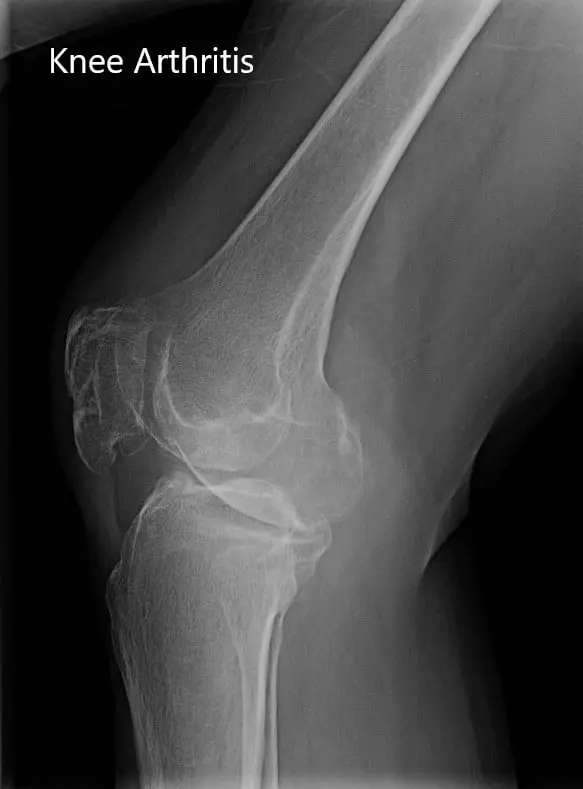

The imaging results revealed severe tricompartmental osteoarthritis of the knee. Considering his lifestyle limiting knee pain, he was advised right total knee replacement with custom instruments. The risks, benefits, and alternatives were discussed with the patient at length. He agreed with the plan.

Preoperative X-ray showing the anteroposterior and lateral view of the right knee.